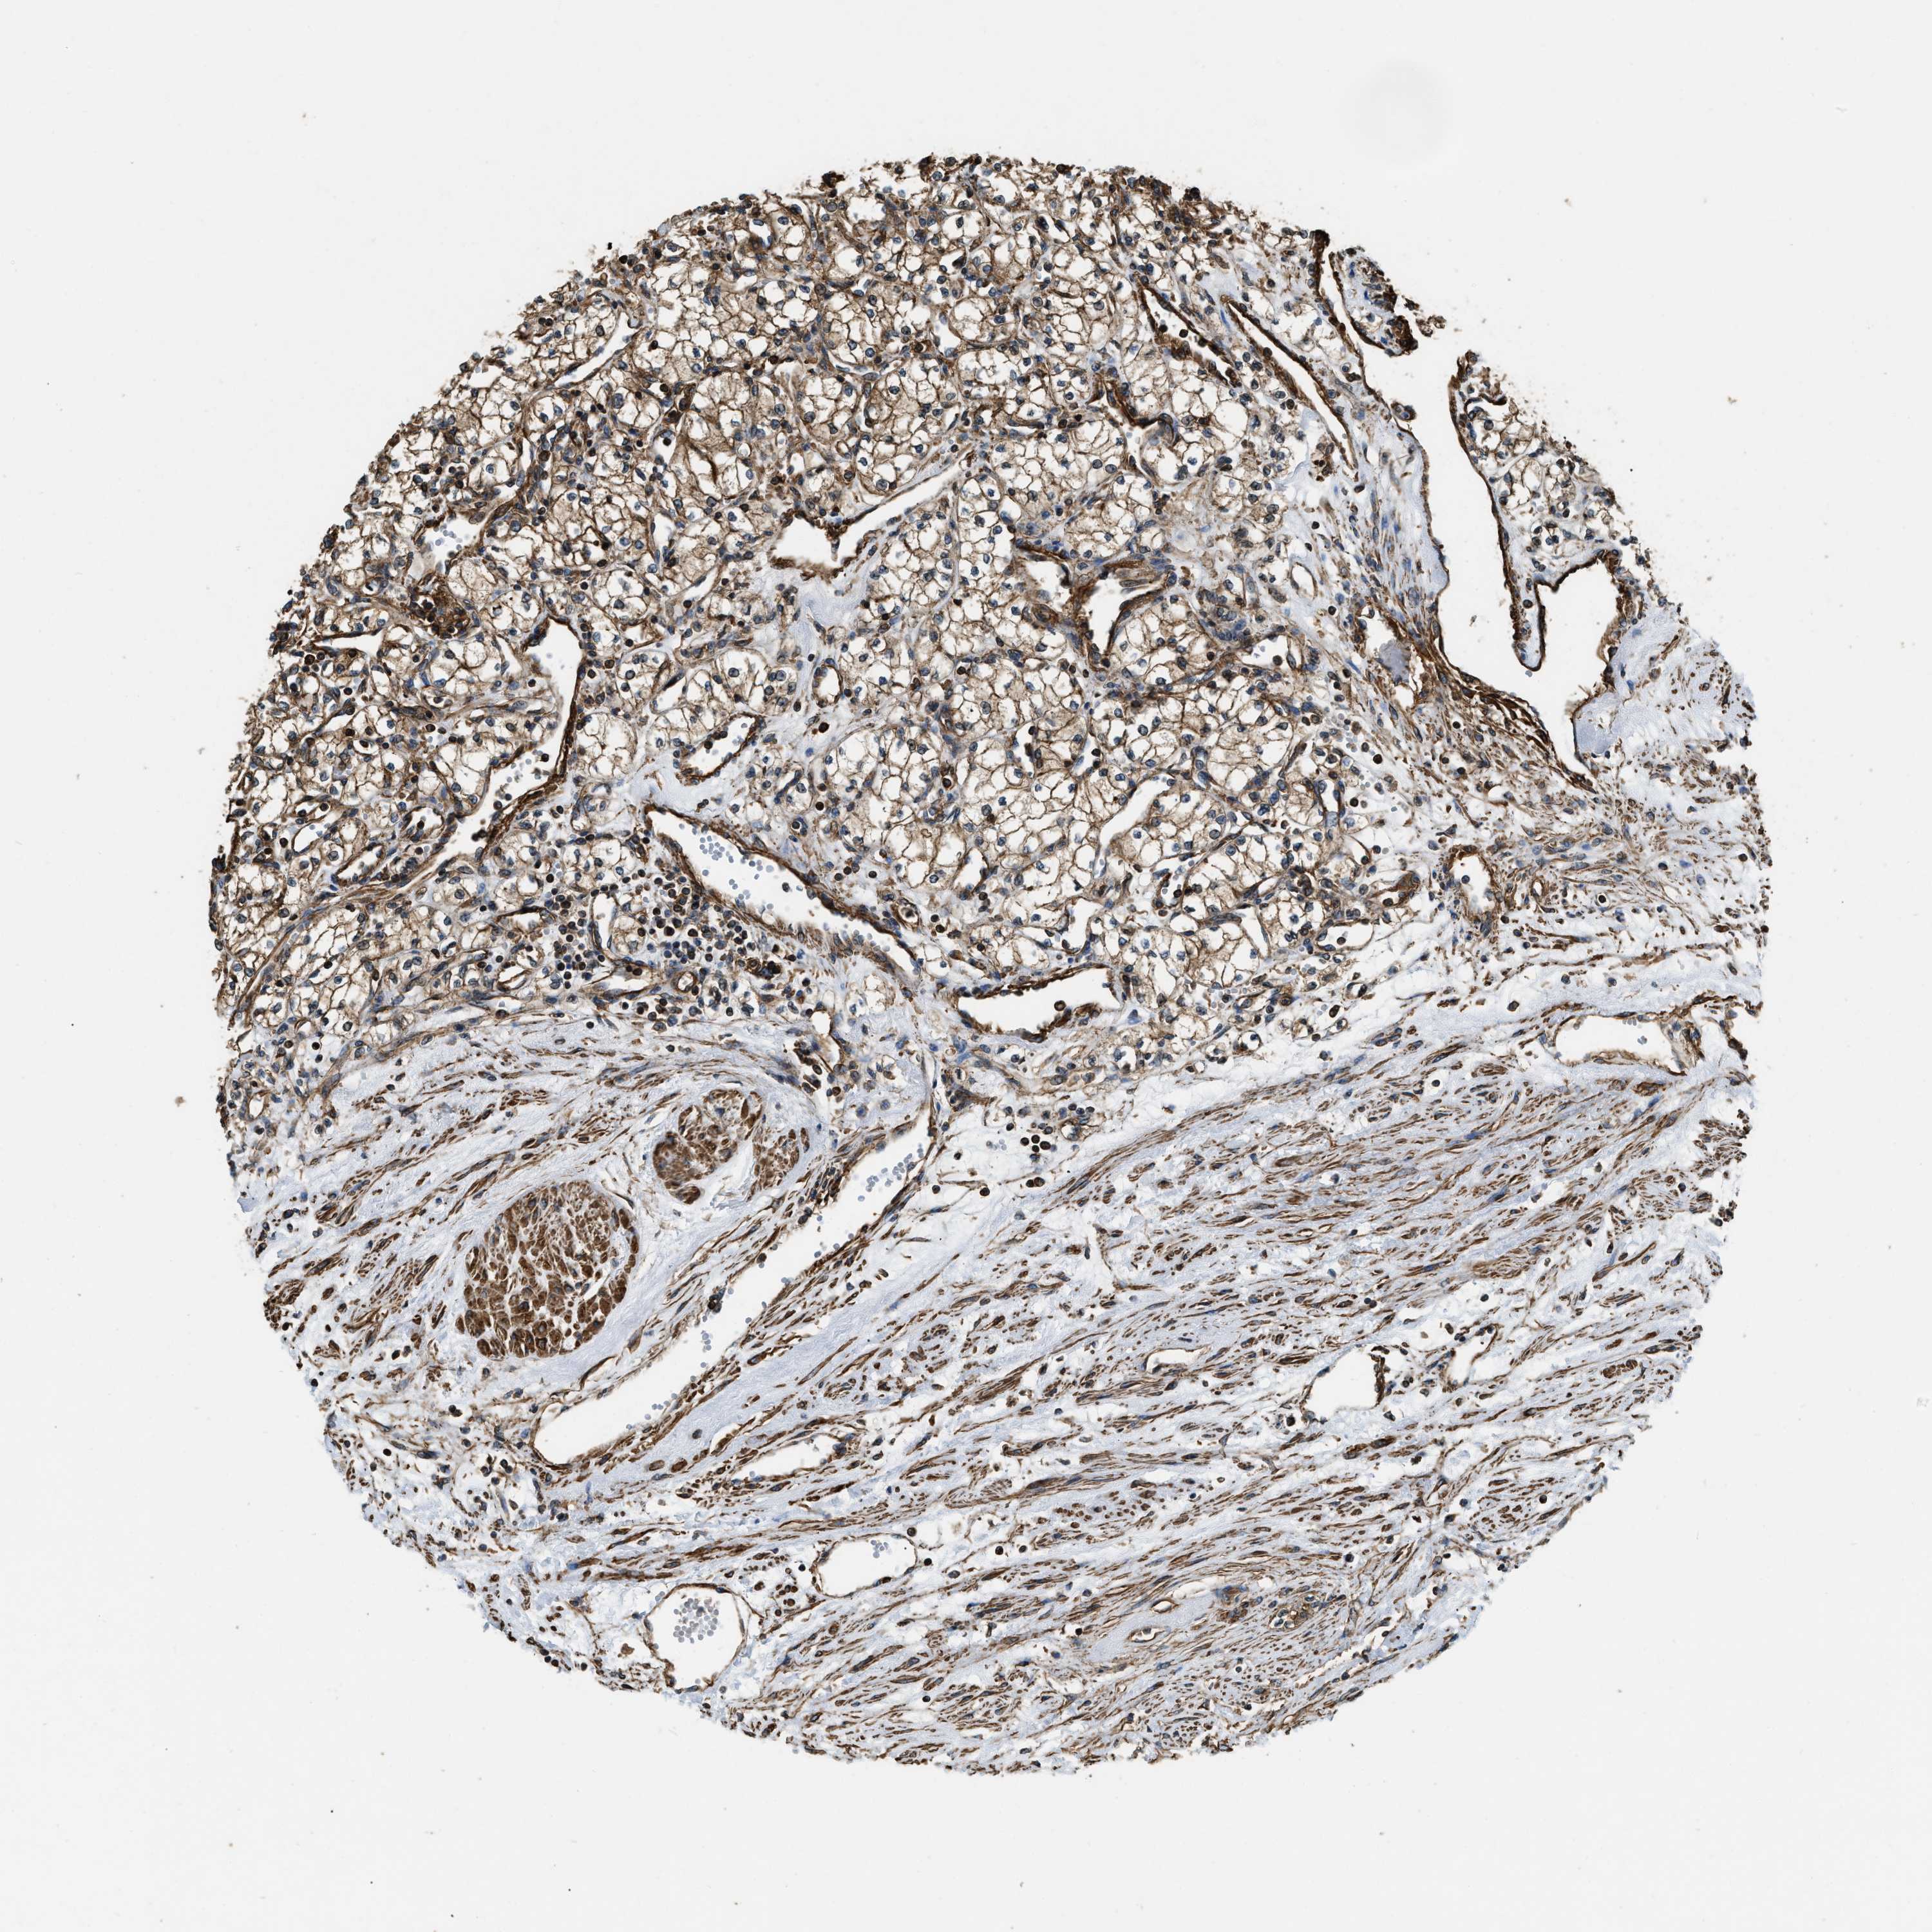

KIDNEY RENAL PAPILLARY CELL CARCINOMA (TCGA) - Interactive survival scatter ploti

The Survival Scatter plot shows the clinical status (i.e. dead or alive) for all individuals in the patient cohort, based on the same data that underlies the corresponding Kaplan-Meier plots. Patients that are alive at last time for follow-up are shown in blue and patients who have died during the study are shown in red.

The x-axis shows the expression levels (FPKM) of the investigated gene in the tumor tissue at the time of diagnosis. The y-axis shows the follow-up time after diagnosis (years). Both axes are complimented with kernel density curves demonstrating the data density over the axes. The top density plot shows the expression levels (FPKM) distribution among dead (red) and alive patients (blue). The right density plot shows the data density of the survived years of dead patients with high and low expression levels respectively, stratified using the cutoff indicated by the vertical dashed line through the Survival Scatter plot. This cutoff is automatically defined based on the FPKM cutoff that minimizes the p-score. The cutoff can be changed by dragging the vertical line or by entering a cutoff value in the square labeled "Current cut-off".

Under the Survival Scatter plot the p-score landscape (black curve; left axis) is shown together with dead median separation (red curve; right axis). Dead median separation is the difference in median mRNA expression between patients who have died with high and low expression, respectively. It is calculated as follows: median FPKM expression of dead patients with high expression - median FPKM expression of dead patients with low expression. This is intended to aid the user in visually exploring custom cutoffs and the associated p-scores and dead median separation.

Individual patient data is displayed and can be filtered by clicking on one or more of the category buttons on the top of the page. Categories describing expression level and patient information include: high, low, alive, dead, female, male and tumor stages. The scale of the x-axis can be toggled between linear and log-scale by clicking on the "x log" button. Mouse-over function shows TCGA ID, patient information and mRNA expression (FPKM) for each patient.

& Survival analysisi

Kaplan-Meier plots summarize results from analysis of correlation between mRNA expression level and patient survival. Patients were divided based on level of expression into one of the two groups "low" (under cut off) or "high" (over cut off). X-axis shows time for survival (years) and y-axis shows the probability of survival, where 1.0 corresponds to 100 percent.

YARS1 is not prognostic in Kidney Renal Papillary Cell Carcinoma (TCGA)

Best expression cut offi

Based on the FPKM value of each gene, patients were classified into two groups and association between prognosis (survival) and gene expression (FPKM) was examined. The best expression cut-off refers the FPKM value that yields maximal difference with regard to survival between the two groups at the lowest log-rank P-value. Best expression cut-off was selected based on survival analysis .

When clicking on this number, the vertical dashed line indicating cut-off, the interactive survival plot, and the Kaplan-Meier curve will be adjusted to show results based on the best expression cut-off.

: 29.76